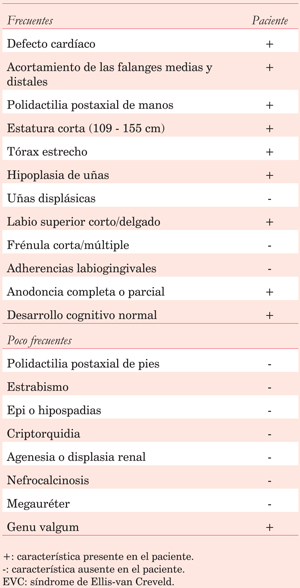

Paciente asintomático que acude a control médico, donde identifican un soplo a la auscultación cardíaca, por lo que es referido a especialista para estudio. Al examen físico se encuentra: talla 133 cm, orejas de implantación baja, anodoncia parcial, paladar íntegro; elevación de hemitórax anterior izquierdo, escoliosis de columna dorsal; cicatriz de resección de dedo supernumerario y uñas hipoplásicas en ambas manos; miembros inferiores más cortos que miembros superiores, miembro inferior izquierdo acortado; rodillas en valgo (Figura 1). En la inspección de tórax se observa choque de punta en región subesternal. En la auscultación cardíaca se aprecian ruidos rítmicos, en foco mitral soplo holosistólico, regurgitante, grado III/VI, irradiado a axila; en foco pulmonar soplo sistólico eyectivo, grado II/VI, con P2 aumentado, desdoblado y fijo.

Figura 1: A. Paciente luego de corrección quirúrgica de defecto cardíaco (esternotomía media), características clínicas descritas en el texto. B. Dedos supernumerarios en la niñez, antes de su resección. C. Anodoncia parcial.

En el electrocardiograma destaca PR prolongado, bloqueo completo de rama derecha y hemibloqueo anterior izquierdo. En la radiografía de tórax se evidencia hiperflujo pulmonar y escoliosis de la columna dorsal con concavidad izquierda (Figura 2). El ecocardiograma transtorácico reportó comunicación interauricular tipo ostium primum de 22 mm, comunicación interventricular de 15 mm totalmente ocluida por velo septal tricuspídeo convirtiendo un canal AV intermedio en un canal AV parcial e hipertensión pulmonar leve.